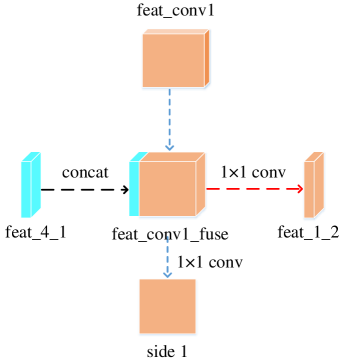

2.3 Top-bottom short connection

Bottom-top short connections aim to refine high-level segmentation results. However, we can observe from the first two rows in Figure 1 that the vessel map generated by the first side-output layer contains too many noises while the map generated by the last side-output could capture the main vessel structure. Therefore, we propose delivering high-level structural information to the first side-output layer to reduce its noises. We implemented this kind of information delivery by a top-bottom short connection from conv4 to feat_conv1, which can been seen in Figure 4. We first convolved the last convolution of conv4 using 1 convolution kernels with size 33. Then the obtained feature map are up-sampled 8 to get feat_4_1. The information (feat_4_1) passed from conv4 are concatenated with feat_conv1 to form feat_conv1_fuse (see Figure 5). At last, one hand hand, we perform a 11 convolution operation on feat_conv1_fuse to get the information (feat_1_2) delivered to feat_conv2. On the other hand, we performed convolution operation with a kernel size of 11 and sigmoid transformation for feat_conv1_fuse sequentially to obtain the segmentation result (side 1). At last, side 1 is compared with the ground truth to get the loss of the first side-output layer.